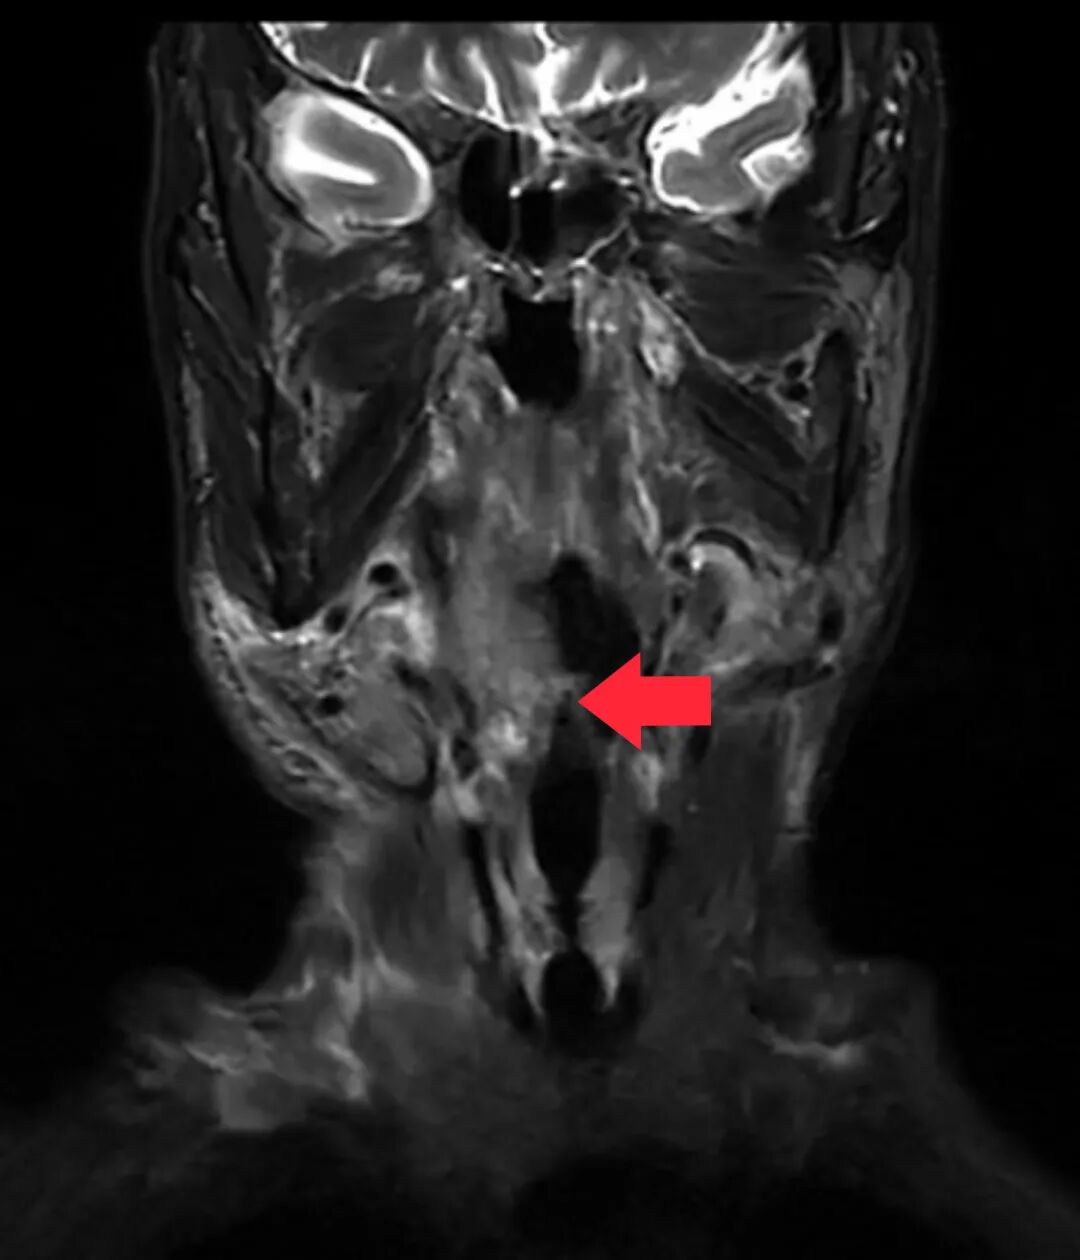

在邓泽义主任医师专业团队及护理团队的照顾下,手术顺利进行,术中肿瘤切除干净。术后,患者短期内经胃管饮食,出院时即可拔除胃管,全流饮食。在此期间,叶大叔主观感觉除喉咙疼痛以外,并无其他不适。结合叶大叔的病情,术后加做辅助放疗。目前叶大叔已结束整个治疗病程,复查MR未见肿瘤残留及复发,悬着的心也放了下来。

△术后及放疗后复查MR